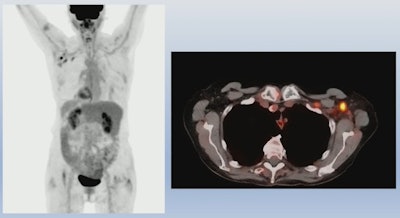

PET/CT imaging shows that COVID-19 mRNA vaccines appear to cause higher rates of reactive lymph nodes in cancer patients compared with whole-virus vaccines, according to a study presented at the American Roentgen Ray Society meeting in Honolulu.

The researchers characterized lymph nodes with FDG radiotracer uptake below or at the blood pool level as nonreactive, while those with FDG uptake above the blood pool level were classified as reactive. Among the patients, 183 received the Pfizer-BioNTech vaccine, 83 received the Moderna vaccine, 11 received the Janssen vaccine, and 64 received CoronaVac.

According to the analysis, patients receiving the Pfizer-BioNTech and Moderna vaccines had similar incidences of reactive axillary lymph nodes in the first 20 days after the second dose (44% for the first 10 days for both groups, and 26% vs. 20% for days 10 to 20). However, Moderna recipients had higher incidences after 20 days than patients who received the Pfizer-BioNTech vaccine (4% vs. 15%).

On the other hand, no incidences of reactive axillary lymph nodes were found in patients who received either a single injection of the Janssen vaccine (full dose) or two doses of CoronaVac. Except for age, other clinical parameters were not predictive, Adin said.